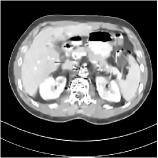

We have conducted experiments on 20 test slices (slice 20, slice 50, slice 100, slice 150 and slice 200 of patient L067, L143, L192, L310) of the Mayo Clinic data. Table I shows the averaged image quality of 20 test images with different methods. From Table I, we observe that Parallel SUPER significantly improves the image quality compared with the standalone methods. It also achieves 1.8 HU better average RMSE compared with Serial SUPER while its SSIM is comparable with Serial SUPER. Fig. 3 shows the reconstructions of L067 (slice 50) and L310 (slice 150) using PWLS-ULTRA, FBPConvNet, serial SUPER (FBPConvNet + PWLS-ULTRA), and parallel SUPER (FBPConvNet + PWLS-ULTRA), along with the references (ground truth). The Parallel SUPER scheme achieved the lowest RMSE and the zoom-in areas show that Parallel SUPER can reconstruct image details better.